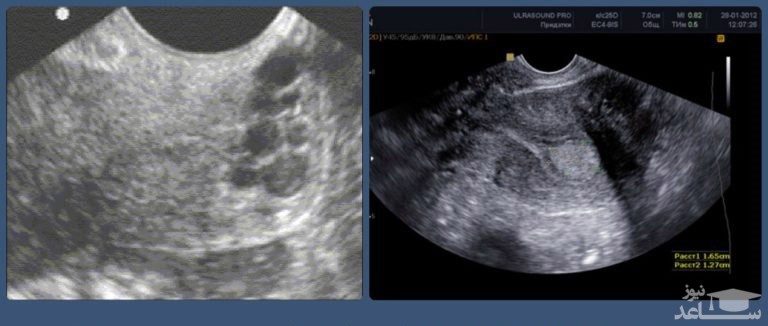

تست های تصویر برداری

الاستوگرافی های تشدید مغناطیسی (MRE) را می توان توصیه کرد.این آزمایش تصویربرداری پیشرفته سخت شدگی و سفت شدن کبد را مشخص میکند. تست های تصویربرداری دیگر مانند MRI، CT و فراصوت نیز ممکن است انجام شوند.